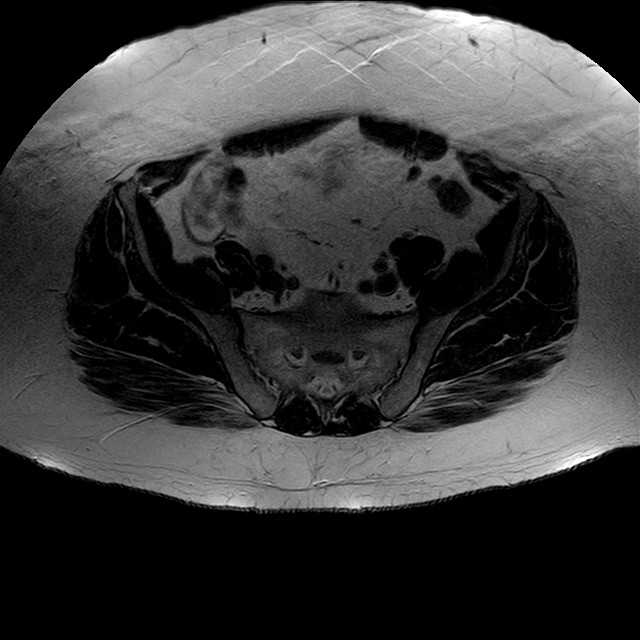

Esami: RMN BACINO

eT2w TSE

Evidenti e simmetriche alterazioni osteofitosiche in regione coxo femorale con riduzione delle rime articolari. Degenerazione completa del cercine glenoideo. Non attuali segni di versamento articolare. Non segni di edema osseo che escludono attuale algodistrofia od osteonecrosi. Lieve e simmetrica riduzione del trofismo della muscolatura glutea.